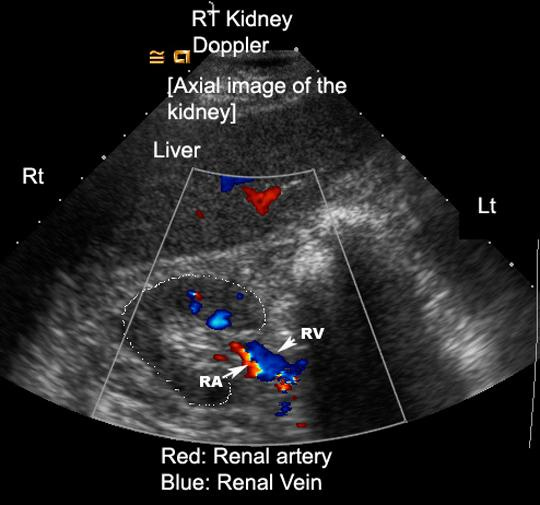

Step 4: Intrarenal Vein Doppler

How to Obtain the View

Coronal approach (xiphoid to posterior axillary line)

Visualize kidney → zoom parenchyma

Use color Doppler to identify interlobar vessels

Place Doppler gate within vein

Interpretation

Continuous → normal

Biphasic → mild

Monophasic (D only) → severe

Pitfalls

Technically difficult

Poor visualization in critically ill

Requires low Doppler scale

Limited evidence in CKD